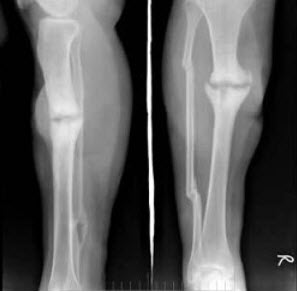

E.自发性纵隔气肿,与间质性肺气肿关系密切

女,48岁,车祸致右胫腓骨骨折,外固定术后两年复查,如图所示,最可能的诊断是()

A.右胫骨愈合延迟

B.右胫骨假关节形成

C.右胫骨骨折愈合好,有大量骨痂形成

D.右胫骨断端不连

E.以上均不正确